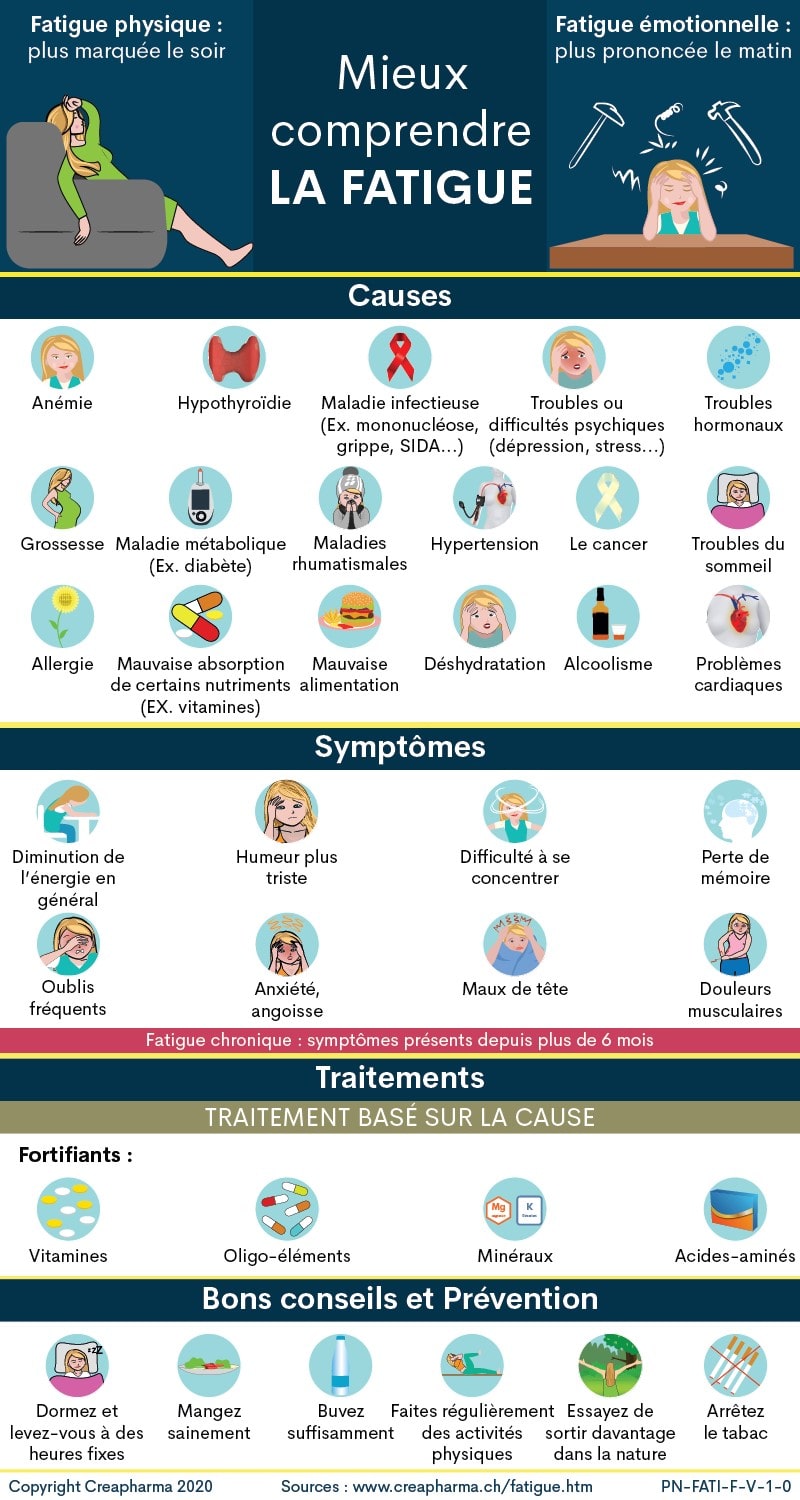

♠ 12

Energie fluctuante  fatigue chronique burnout boreout Causes, Symptomes, Solutions… (Hors TDAH)  Cliquez pour agrandir |

► La